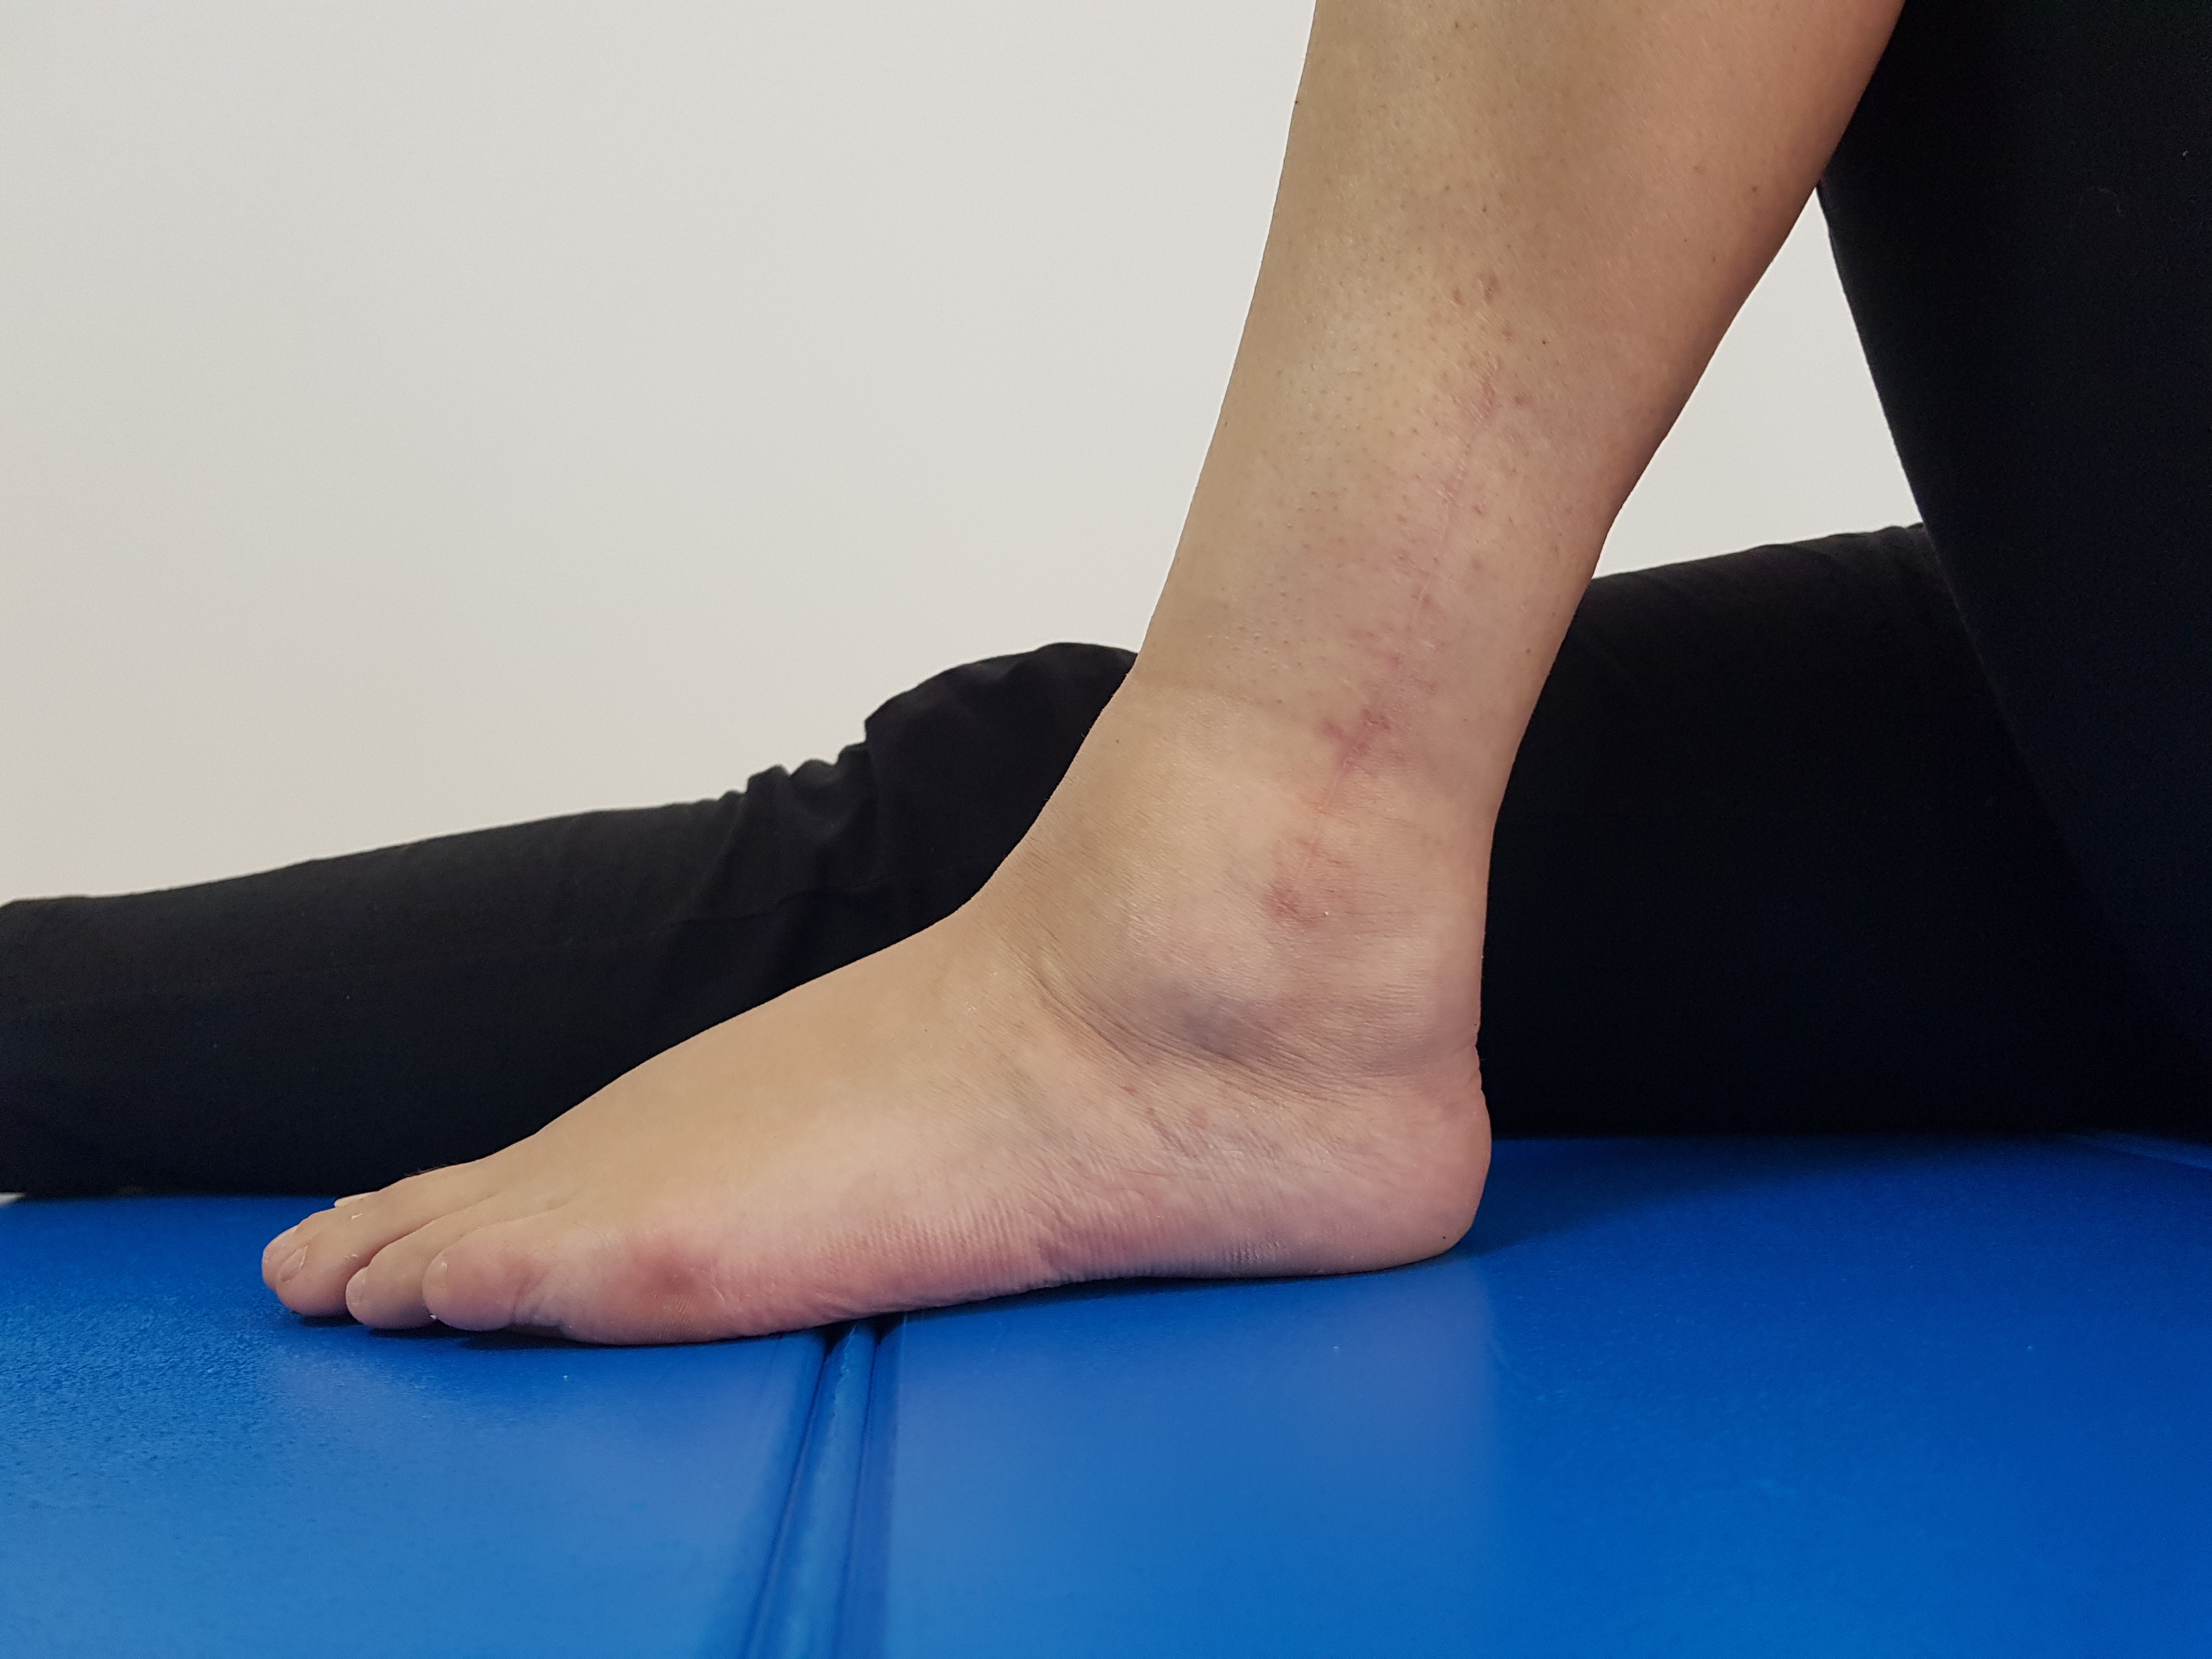

FRACTURA TRIMALEOLARA STANGA